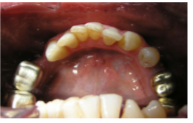

3. Presence of teeth

-UR7--- UR3UR2---UL3UL4UL5----

-LR7LR6--LR3LR2LR1LL1LL2LL3LL4--LR6--

4) Restorations of upper and lower teeth